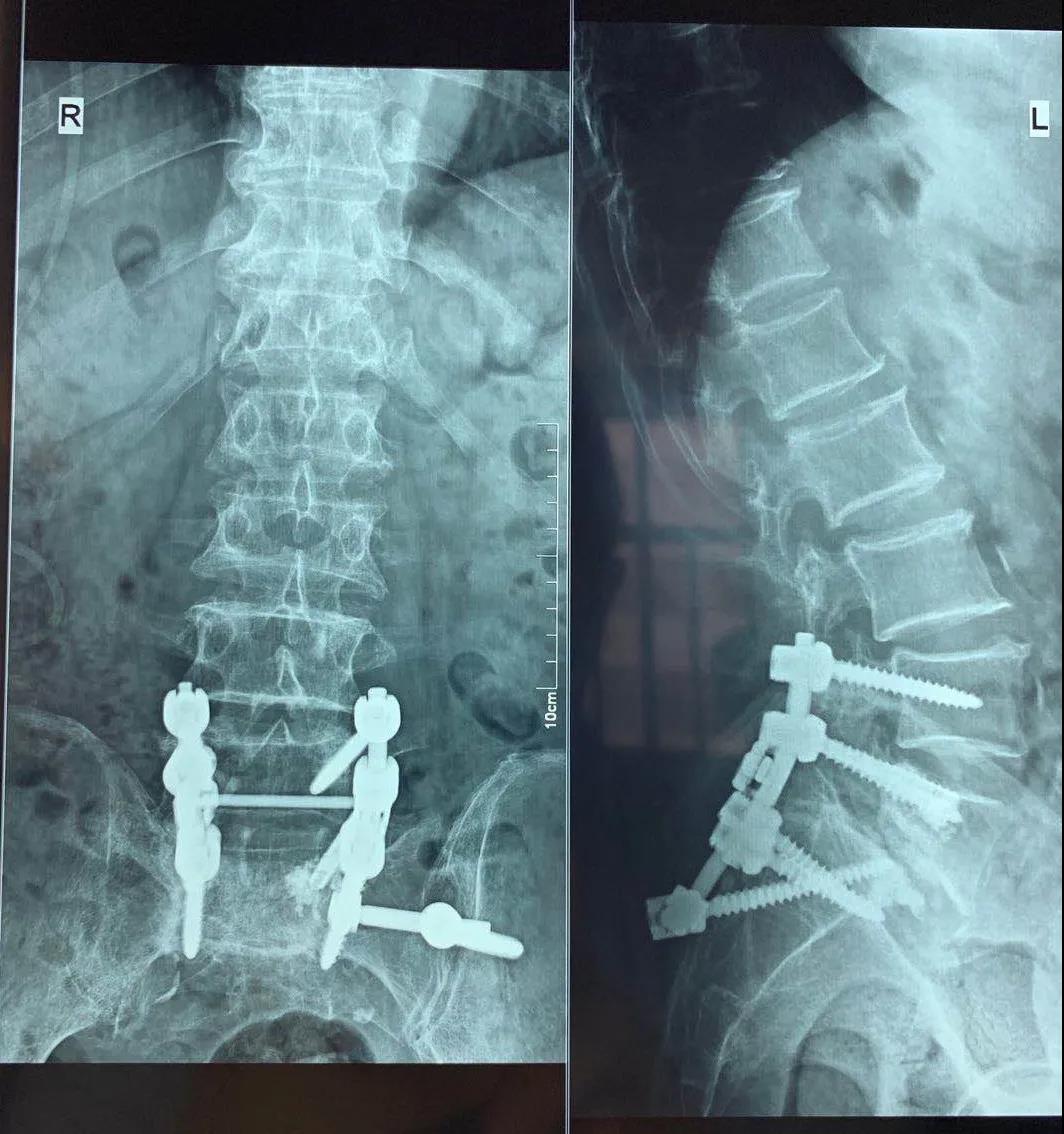

近日,醫(yī)院骨二科成功完成復雜腰椎內固定翻修手術一例,患者為77歲老年男性,因腰椎滑脫(3度)于2020年5月2日在外院行腰椎后路滑脫復位內固定及椎間融合術,術前患者能自行行走,術后出現(xiàn)腰痛及下肢后側疼痛,并雙髖及雙膝關節(jié)屈曲伸直活動受限,伸直受限于屈曲110°位,經外院康復理療不能好轉,于2020年6月4日來醫(yī)院骨二科就診。骨二科主任許冬雷為其進行了X線檢查,檢查提示腰椎滑脫內固定裝置失效導致再次滑脫,并椎間融合器部分脫出至椎管,給予收住院治療,完善腰椎CT及頸椎磁共振,并組織科內討論,詳細查體及仔細研讀影像學資料。

手術前后對比

手術前

手術后

科室綜合分析患者現(xiàn)在的病情,考慮手術內固定失效是引起癥狀的主要原因,決定給予行腰椎滑脫內固定翻修術,在院領導、麻醉科和手術室的支持下,充分論證手術可能存在的風險及相關處理方案,向患者及家屬詳細的介紹病情及治療方案,取得患者及家屬的同意,完善術前準備,骨二科許冬雷專家團隊于6月23日全麻下行腰椎滑脫內固定失效翻修術,術中給予去除移位的椎間融合器,更換腰5左側的椎弓根螺釘,考慮患者為骨質疏松患者,更換的椎弓根釘為骨水泥型椎弓根釘,并考慮患者單純骶1螺釘固定應力較大,給予增加左側髂骨釘固定,術中透視確認內固定位置,手術順利,患者入ICU監(jiān)護治療,術后第一天患者自述腰痛及下肢疼痛消失,雙下肢自主活動及感覺正常,雙膝伸直受限明顯好轉,可伸直至80°,術后三天出ICU返回病房,給予復查X線平片及CT檢查,見滑脫椎體大部復位,并更換的椎弓根螺釘及髂骨釘位置良好,繼續(xù)給予理療及功能鍛煉,現(xiàn)能主動伸直至膝關節(jié)屈曲60°位,下一步擬患者腰部手術恢復后行頸椎微創(chuàng)射頻治療,緩解患者的髖膝周圍肌肉張力,進一步緩解患者的髖膝關節(jié)功能。